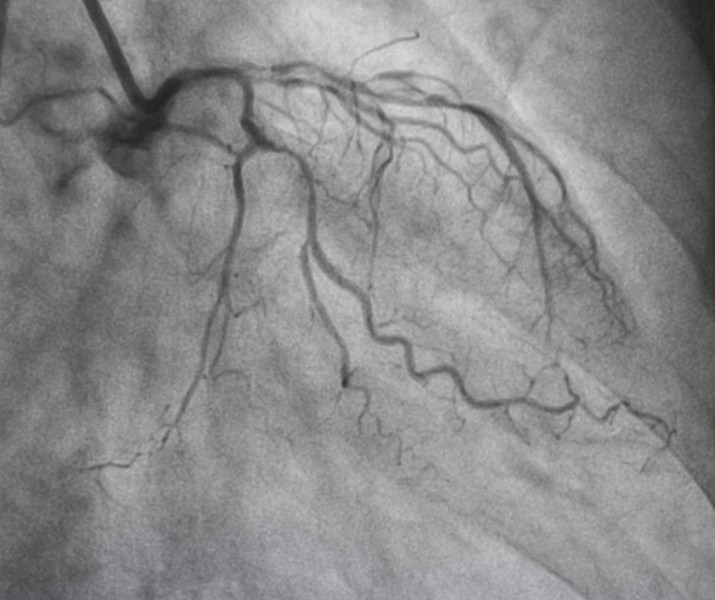

تكمن أهمية القسطرة القلبية في أنها تساعد الطبيب على رؤية الشرايين التاجية من الداخل، والتأكد من وجود تضيق أو انسداد يؤثر على تدفق الدم. هذا مفيد جدًا خاصةً عند المرضى الذين يعانون من أعراض مثل ألم الصدر، ضيق التنفس، أو نتائج فحوصات غير طبيعية في رسم القلب أو اختبار المجهود. وتُستخدم القسطرة كذلك في تقييم كفاءة عضلة القلب وقياس الضغط داخل حجراته، وهو ما يجعلها وسيلة تشخيصية لا غنى عنها في معظم الحالات التي يُشك الطبيب في وجود مرض قلبي.

يتم بعدها حقن صبغة طبية داخل الشريان، وتسمى “الصبغة التاجية”، وهي تساعد الطبيب على رؤية تدفق الدم وتحديد أماكن الانسدادات أو التضيق. وخلال هذا الوقت قد يشعر المريض بدفء بسيط في الجسم، وهو أمر طبيعي تمامًا.

يتم إجراؤها بهدف تشخيص مشاكل القلب دون أي تدخل علاجي. تكمن أهميتها في أنها تساعد الطبيب على رؤية الشرايين التاجية بدقة، وتحديد مدى وجود تصلب شرياني، وتقييم كفاءة عضلة القلب، وقياس الضغط داخل حجرات القلب. تُستخدم القسطرة التشخيصية خاصةً عند المرضى الذين يعانون من ألم الصدر غير المفسر أو نتائج غير طبيعية في فحوصات القلب. وهي الخطوة الأولى قبل اتخاذ أي قرار بشأن العلاج سواء كان دوائيًا، دعامة، أو جراحة تحويل مسار الشرايين.